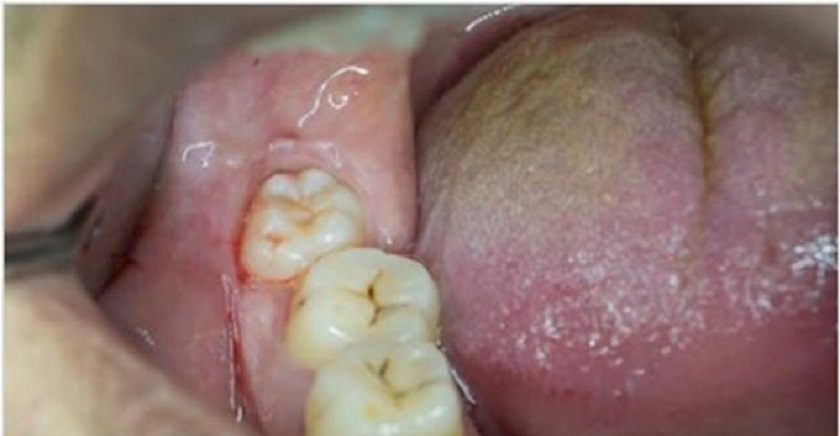

Trong trường hợp mọc răng khôn bị đau, thường là do răng khôn đó mọc thấp, mọc không hoàn toàn hoặc mọc lệch. Điều này làm cho răng khôn không thể mọc hẳn lên được, gây ra tình trạng lợi phủ trên mặt răng khôn, để lại một túi chứa thức ăn, gây viêm nhiễm và đau kéo dài, có thể tái phát nhiều lần. Trường hợp này đau sẽ khá dai dẳng, mỗi 1 lần đau thường kéo dài từ 5 – 10 ngày và hay tái phát thường xuyên. Nếu muốn hết đau, bạn cần phải có sự can thiệp của bác sĩ nha khoa ngay lập tức.

Ngược lại với tình trạng răng khôn mọc thẳng, thì cũng có tình trạng bị lợi trùm răng khôn. Lúc này bác sĩ sẽ cắt lợi trùm để loại bỏ túi lợi nằm trên bề mặt răng khôn.